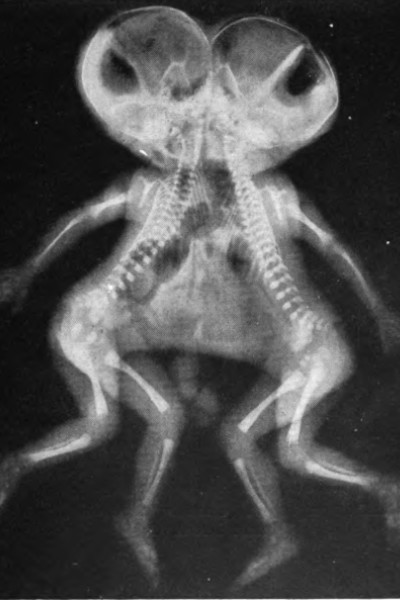

Image credit: Herman Klapproth / Wikimedia Commons